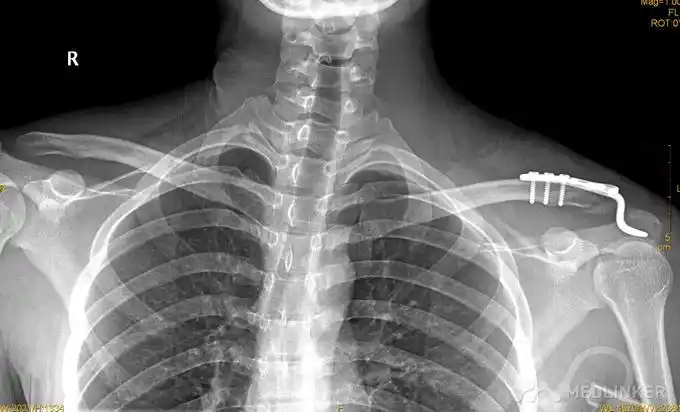

人类肩关节的x光片,显示上臂的肱骨,锁骨(锁骨),肩胛(肩胛骨)和胸腔.